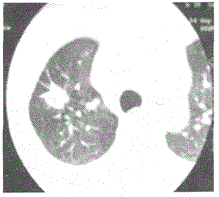

女,61,咳嗽,咯血,CT平扫如图,最可能的诊断是A.肺结核B.周围型肺癌C.中央型肺癌D.炎性假瘤E.错构瘤

选项 A.肺结核 B.周围型肺癌 C.中央型肺癌 D.炎性假瘤 E.错构瘤

答案 B